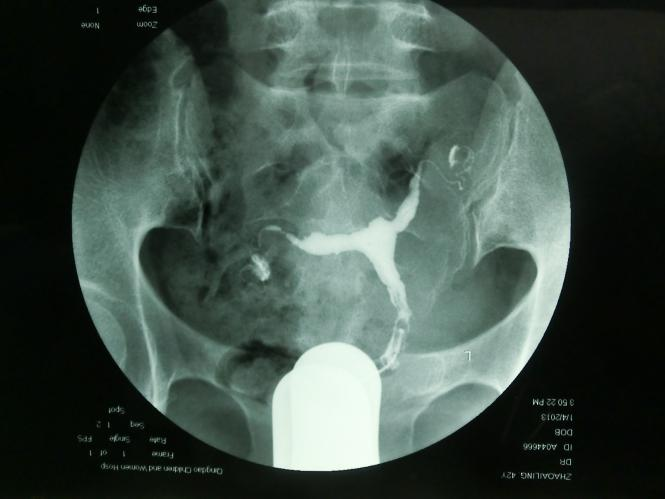

T型子宫有先天性和获得性之分,先天性是指患者胎儿期苯甲酸雌二醇(diethylstilbestrol,DES)宫内暴露或其他因素导致的先天畸形,成因为周边肌肉肥厚,致子宫腔近心端狭窄,中下段侧壁靠近,宫底可略内突,整个宫腔呈“ T ” 型外观(图1),宫体和宫颈长度比2:1。可导致不孕,反复流产,异位妊娠,宫颈机能不全,早产和围产儿死亡。获得性为宫腔粘连后、纤维瘢痕组织的形成,扭曲、塞满或闭锁宫腔,致其宫腔形态酷似“ T ”形,宫腔粘连的组织结构复杂,其边缘不规整,欠规则(图2),获得性T型子宫也与生殖道结核和子宫腺肌症相关,常导致不孕、复发性流产(recurrent pregnancy loss,RPL)和反复种植失败(repeated implantation failure,RIF)。

图1 先天性T型子宫HSG图片